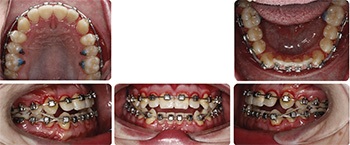

Initially, I started with upper braces only and a Class 3 bite ramp (Fig. 3) to disclude and simulate (b) See my previous article on Class 3 ramps in last month’s issue of Orthotown. Four months later (Fig. 4), lower braces were put on, and I bonded caplin hooks to the lingual of all molars for full-time (alternating crossbite pattern) vertical elastics to erupt the posterior teeth to meet the new vertical goal of (b).

Alternating crossbite pattern vertical elastics to lingual caplin hooks is the best way to erupt posterior teeth without changing their inclination as they extrude. If I had to do it over again, I would have started with these vertical elastics from Day One. The patient did a great job with the vertical elastics, and at month seven (Fig. 5) the molars were in contact, and the bite ramp was removed.

At this point Ethan’s new vertical position matched (b), and the molars had erupted into contact to support this position. The vertical elastics continued, now just at night, through most of his remaining months in treatment to prevent relapse of the extruded molars and loss of the new vertical position. Some Class 3 elastics were used as well, but vertical elastics were the most heavily used.

Figure 6 shows progress through month 16. Upper incisors were not flipped, and SAP bracket positioning (à la Tom Pitts) was used to cheat the occlusal plane in favor of more upper incisor show (Class 3 patients are quite often deficient in vertical incisor show). A noticeable change in the occlusal plane is apparent on cephalometric comparison, reflective of this SAP bracket positioning. This increased vertical incisor show is expressed well within his now decompensated (taller) smile window allowed by (b).

The case finished in 21 months (Figs. 7–10). Ethan will be monitored until growth is complete, and he and his mom are aware of the possibility of relapse if remaining growth is unfavorable.